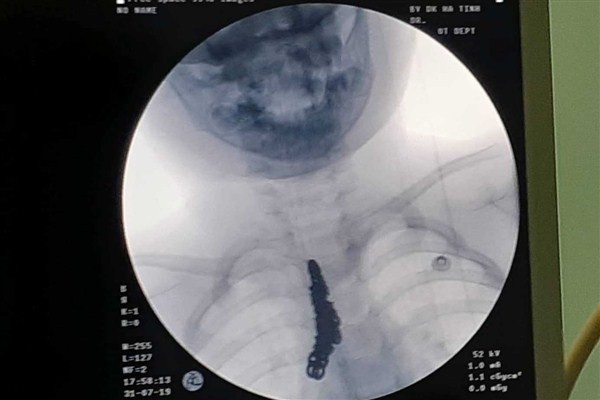

| Phim chụp X-quang cho thấy bé trong vùng ngực của bé trai có dị vật dài là sợi dây chuyền. |

Sau khi thăm khám, chụp phim X-quang và tiến hành nội soi khí quản, các bác sĩ phát hiện dị vật nằm ở khí quản và phế quản gốc bên phải và gắp ra được 1 sợi dây chuyền bạc có kích thước dài 14cm.